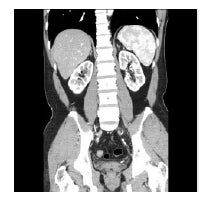

◇Ai写真も豊富に掲載!遺体を傷つけずに調べることができるAi(オートプシー・イメージング)の写真を多用し、リアルなカラダを見ることができます。